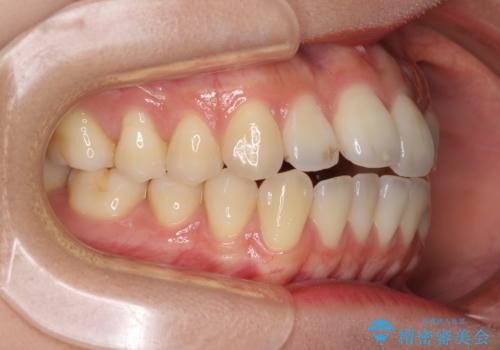

オープンバイトでかみにくい インビザラインによる矯正治療

- 前歯の上下スペースによる食べにくさを気にして来院された患者様です。

インビザラインにより上下の前歯の隙間を閉じていくこととしました。

上下の奥歯を圧下させるようにすることで、前歯を接触させるように計画しました。

上下の隙間に舌が入り込むことがオープンバイトの原因であったため、舌の筋肉のトレーニングも並行して行い、後戻りの抑制を図りました。